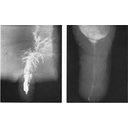

Image showing radiograph of mammary gland.jpg